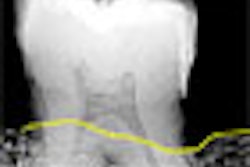

Cone-beam CT developer Imtec of Ardmore, OK, has launched Iluma Elite, a new addition to the company's line of Iluma cone-beam CT scanners.

Elite offers faster reconstruction times, greater storage space, and improved software functions, according to the company. The new system enables faster patient throughput, and also features multiple reconstructions of patient data, at a radiation dose that is lower than conventional medical CT scanners.